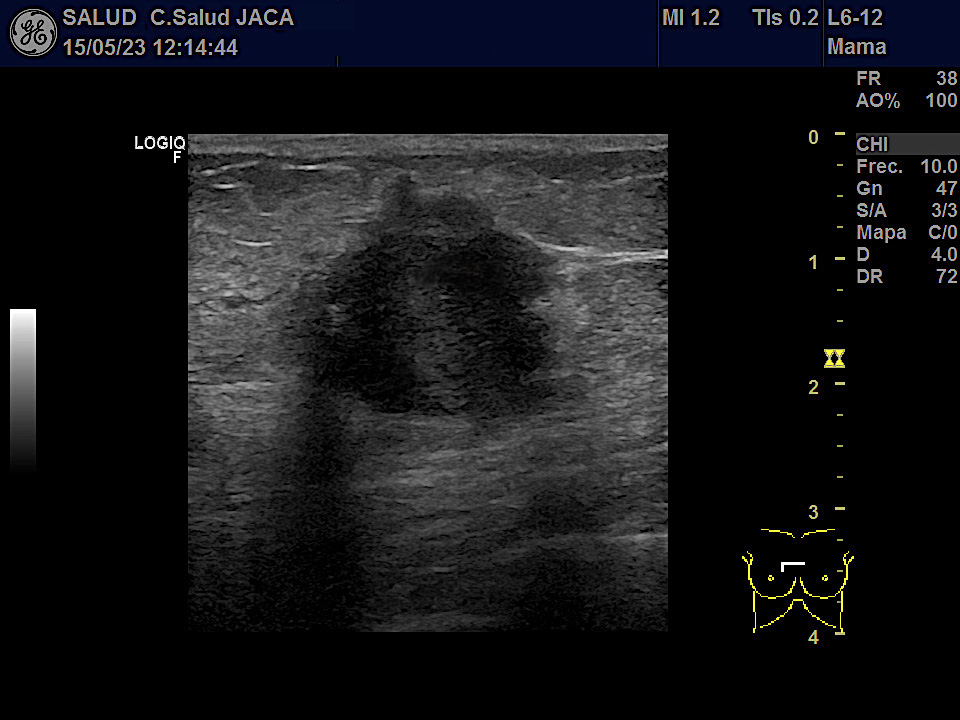

Mostramos las imágenes ecográficas de cada una de esas 5 neoplasias obtenidas desde la Atención Primaria, en modo 2D y tras estudio Doppler. Los tumores variaban de 8 a 30 mm en su eje mas largo. Salvo uno, el resto mostraba características típicas: bordes irregulares, espiculados, estructura hipoecogénica, actividad Doppler interna y ausencia de refuerzo posterior.